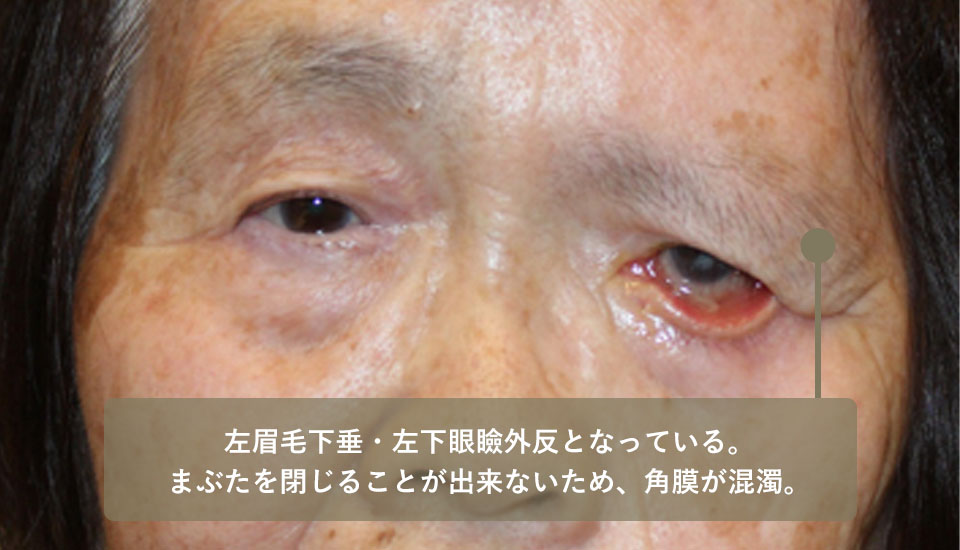

She had left visual field disturbance due to left eyebrow ptosis as a result of left facial nerve palsy.

She had left eyebrow ptosis and a brow lift was desirable, but since the left upper eyelid skin had already been removed, a brow lift could not be performed alone, so a skin graft from the right upper eyelid was performed simultaneously.

Sequential surgery for the left lower eyelid ectropion and hyaluronic acid injections into the right laugh lines were also performed to improve her facial appearance.

| Before surgery | The left eyebrow is droopy and the left lower eyelid is ectropion. The cornea has become cloudy due to the inability to close the eyelid. |

|---|---|

| After surgery | Left eyebrow drooping and left lower eyelid ectropion, exposing the back of the eyelid |

This is a pre-treatment photo of the patient when she first came to our clinic.

Because the previous doctor removed the skin of the upper left eyelid, the amount of the upper eyelid differs greatly between the left and right eyelids.

After surgery, the appearance was considerably improved.

She underwent surgery to raise her left eyebrow, skin grafting from the right upper eyelid to the left upper eyelid, and an exenteration of the left lower eyelid.

She also had hyaluronic acid injections into her laugh lines.